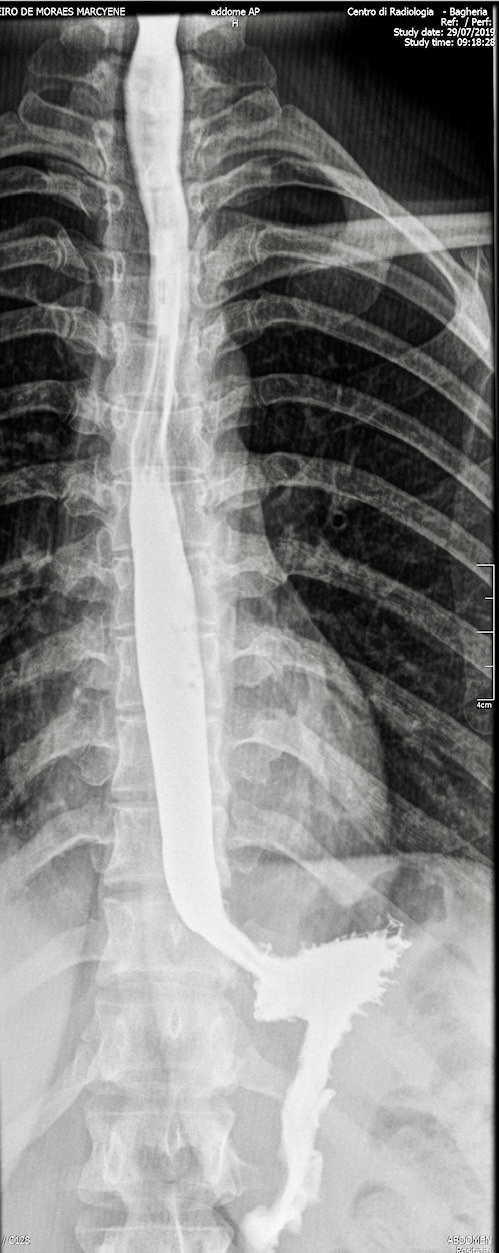

Vengono eseguiti esami radiografici digitali diretti e contrastografici dell’addome per lo studio delle patologie intestinali con la presenza del medico radiologo. È possibile prenotare:

- radiografie all’esofago, stomaco e duodeno;

- video-fluoro-grafia dell’esofago;

- radiografie all’apparato digerente.